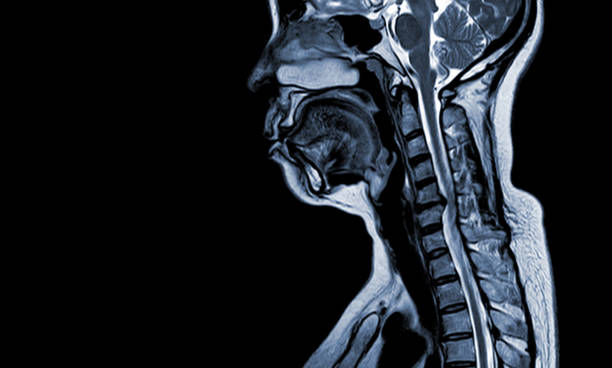

척추협착증은 척추의 추간공이 좁아져 척추 신경이 압박되는 질환입니다.

이로 인해 통증, 저림증, 근력 약화 등의 증상이 나타납니다. 이번 글에서는 척추협착증을 치료하기 위한 다양한 방법을 알려드리겠습니다.